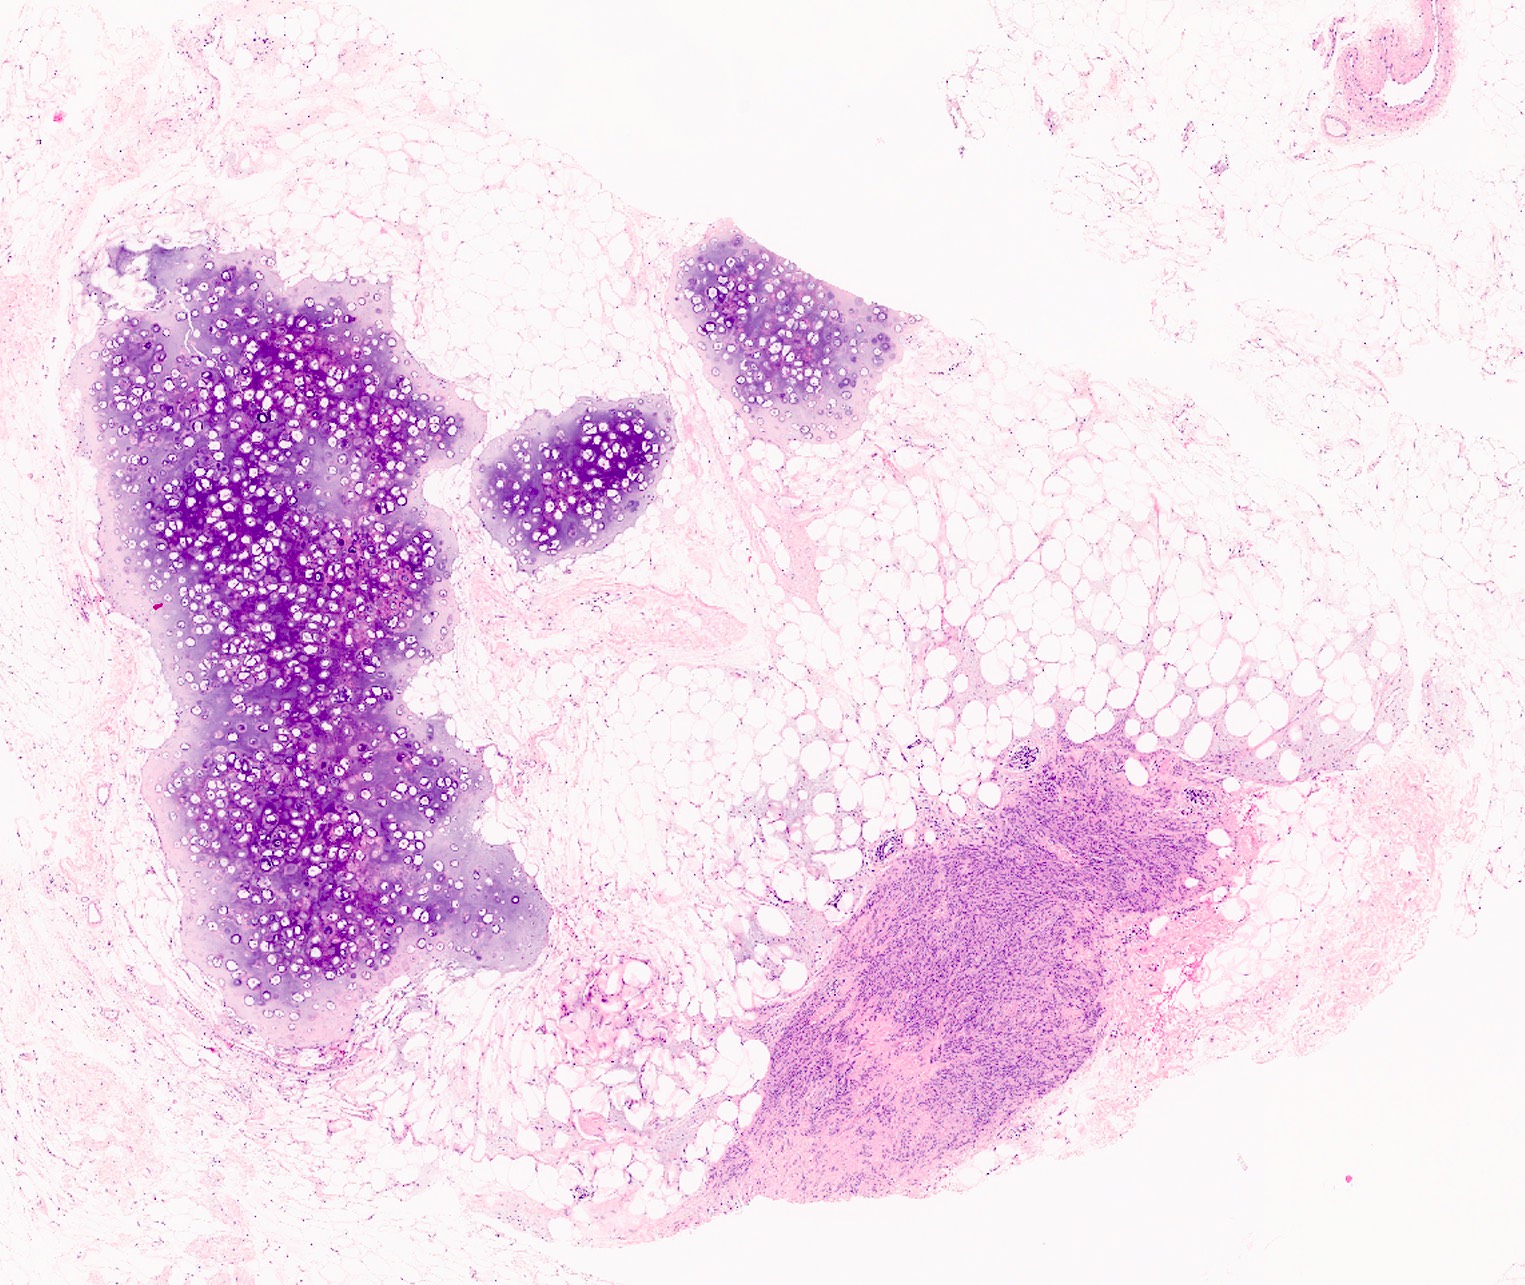

Microscopic (histologic) description

- Well circumscribed, lacks true capsule, rarely infiltrative

- Bland, uniform, short to elongated spindle cells arranged as short haphazard intersecting fascicles admixed with bands of hyalinized, brightly eosinophilic collagen and variable amounts of fat

- No more than mild nuclear atypia

- Mitoses usually absent, atypical mitoses and necrosis absent

- Mast cells common, perivascular lymphocytic infiltrates on occasion

- Focal myxoid stromal changes common

- May show smooth muscle leiomyomatous differentiation (elongated spindle cells with cigar shaped nuclei and pink cytoplasm)

- Rarely cartilaginous or osseous components

- Variants:

- Collagenized / fibrous: collagenous stroma predominates, may have hypocellular myofibroblastic spindle cell component

- Cellular: dense proliferation of myofibroblasts, ratio of spindle cells to collagen increased compared with classical variant, may have infiltrative borders, storiform or herringbone arrangement

- Infiltrative: irregular margins, grows into surrounding mammary parenchyma entrapping glandular tissue

- Myxoid: stellate and spindle cells in abundant myxoid stroma (Histol Histopathol 2016;31:1)

- Deciduoid: large round, polygonal cells with abundant eosinophilic glassy cytoplasm, single or multiple prominent nucleoli which may be eccentrically placed, binucleation, sharp cell borders, eosinophilic intracytoplasmic inclusions (Histopathology 2008;52:652)

- Lipomatous: abundant adipocytic component

- Epithelioid: oval to polygonal cells arranged in clusters, cords, alveolar groups, linear strands, mono, bi or multinucleated, may have eccentrically placed nuclei with small nucleoli, well defined cell borders, single file arrangement may mimic invasive lobular carcinoma (Am J Surg Pathol 2009;33:1085)

- Atypical: single or scattered atypical mono or multinucleated cells with mild to severe nuclear pleomorphism, regarded as degenerative (Arch Pathol Lab Med 2008;132:1813)

Microscopic (histologic) images